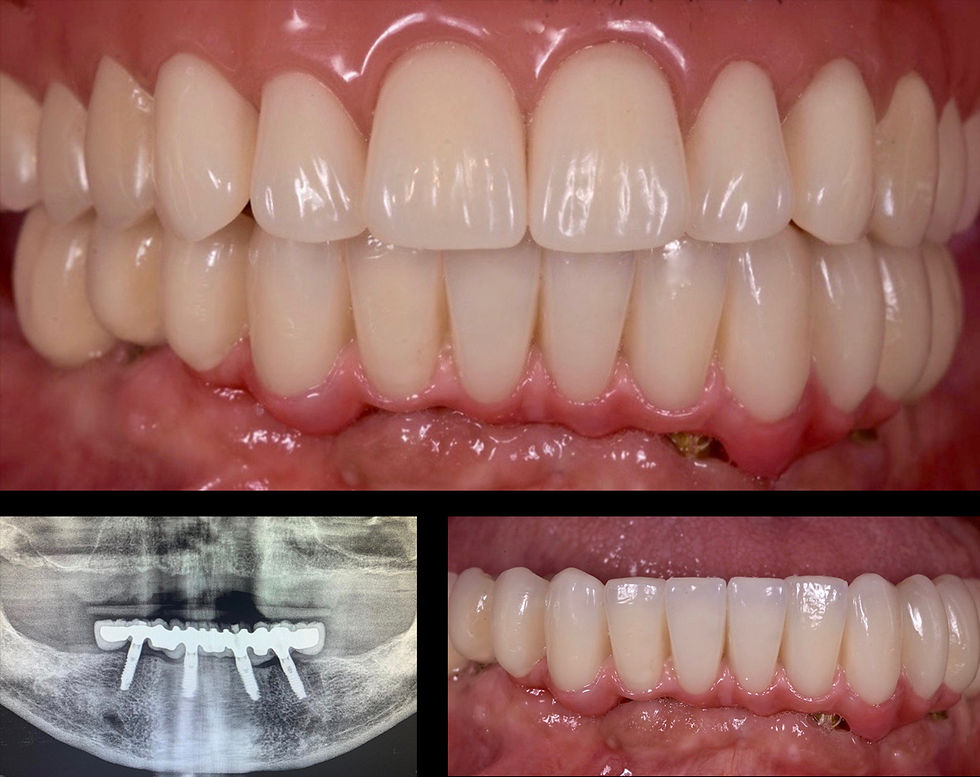

Provisional prosthesis at delivery and x-ray check

Delivery of both final prosthesis

Vision of the interrelationships between jaws: the II prosthetic class was brought to the I class in the cusp-fossa so that no movements of the upper prosthesis were generated